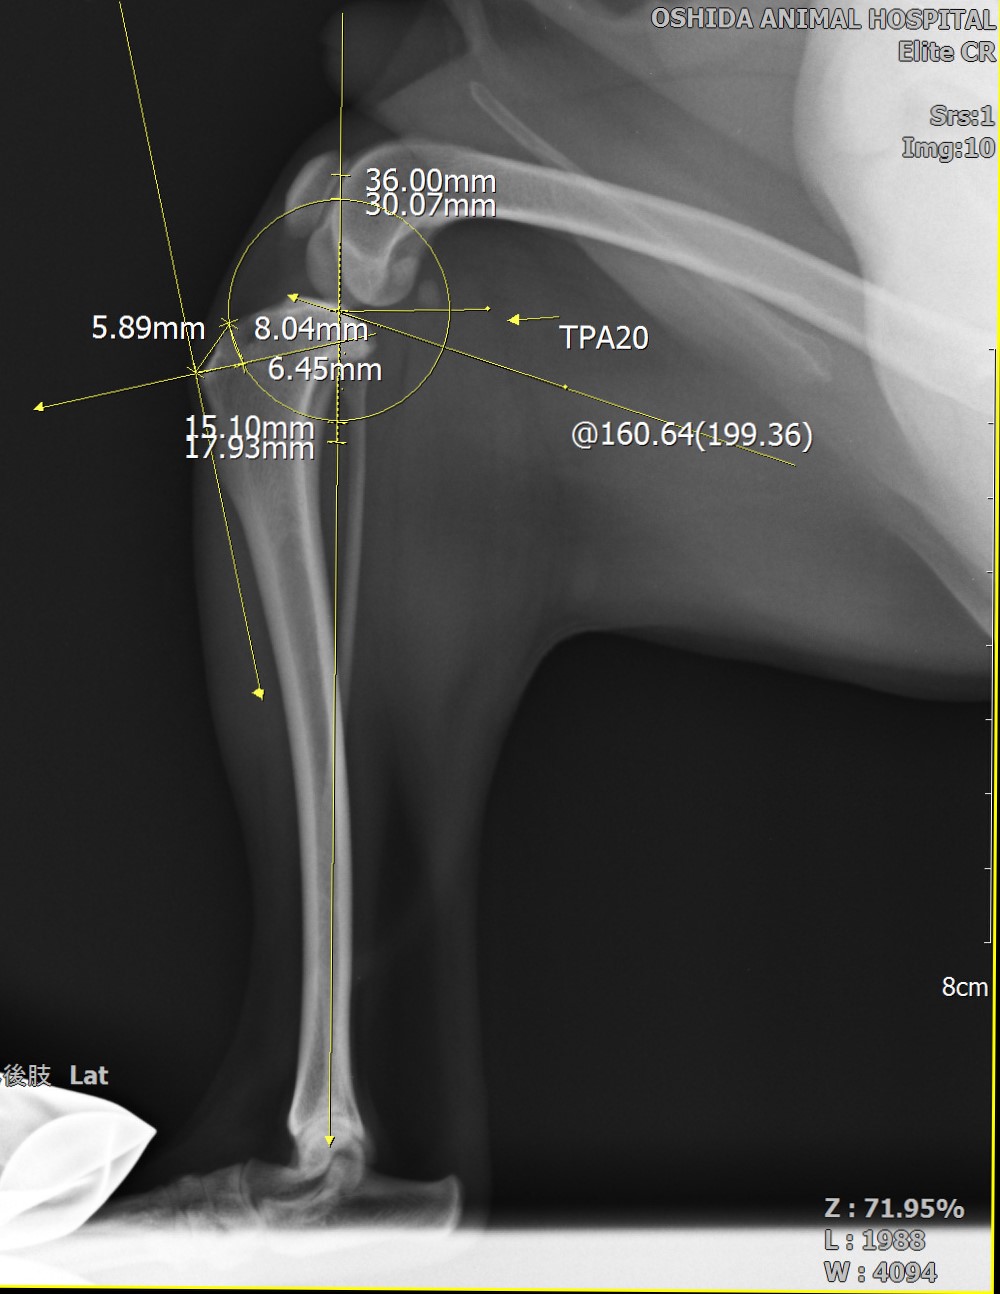

前十字靭帯断裂制動術(TPLO法・術前プランニング)

骨切りを行う前にインプラントの適応など入念な手術計画が必要です